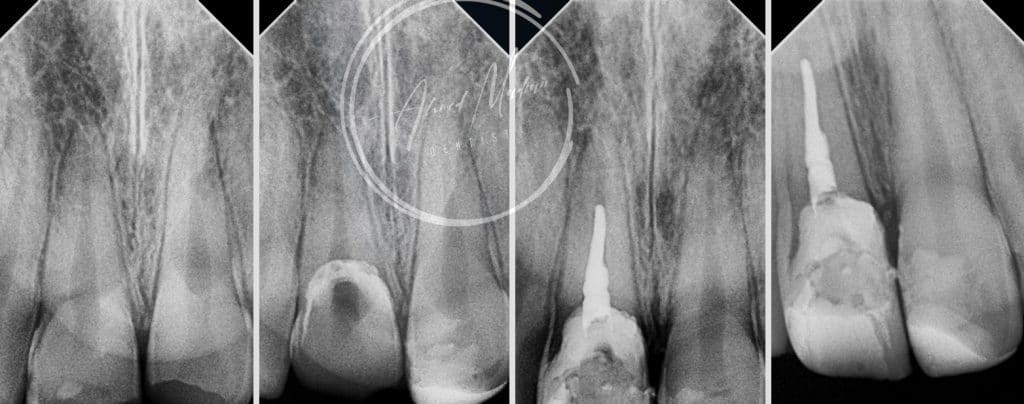

14 y male patient came to the office complaining of trauma in the anterior region

After clinical and radiographic examination , senstivity , mobility assessment

Tooth no 11 showed complicated crown root fracture , exposed pulp , closed apex

Tooth no 12 uncomplicated corwn fracture , class lV

11 – gingivectomy , DME , build up , cleaning and shaping , intra canal medication and patient will be under follow up for the next month considering the initiation of internal or external resorption , after follow up RCT , fiber post will be placed